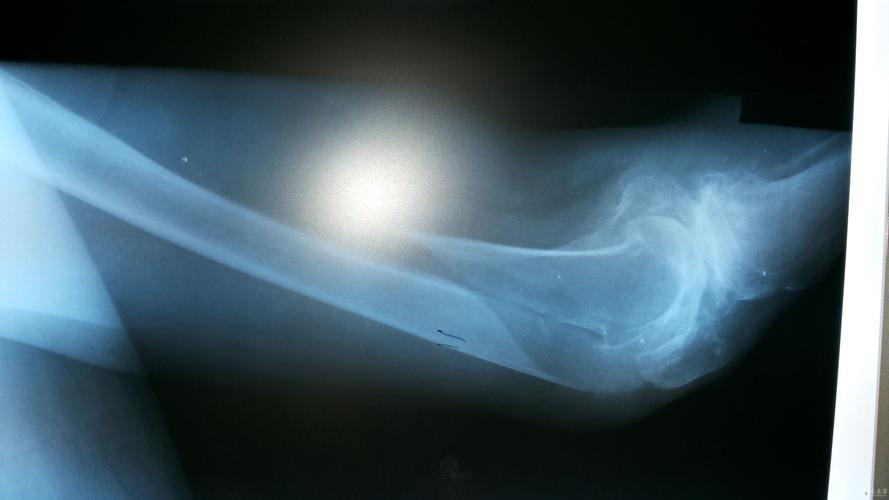

肱骨骨折术后六周求助(附片)

90岁股骨远端长螺旋形骨折